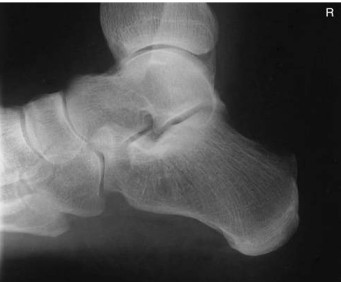

Name what anatomy is demonstrated in this projection of the foot

entire foot should be demonstrated along with 1 inch (2.5 cm) of distal tibfib. Distal fibula seen superimposed over posterior half of tibia, and plantar surfaces of heads of metatarsals should be superimposed if no rotation is present. The longitudinal arch of the foot must be demonstrated in its entirety

What is the correct CR angle and centering point for this projection?

CR 40 degrees cephalad from long axis of foot (40 degrees from vertical if long axis of foot is perpendicular to IR), CR to base of third metatarsal to emerge at a level just distal to lateral malleolus